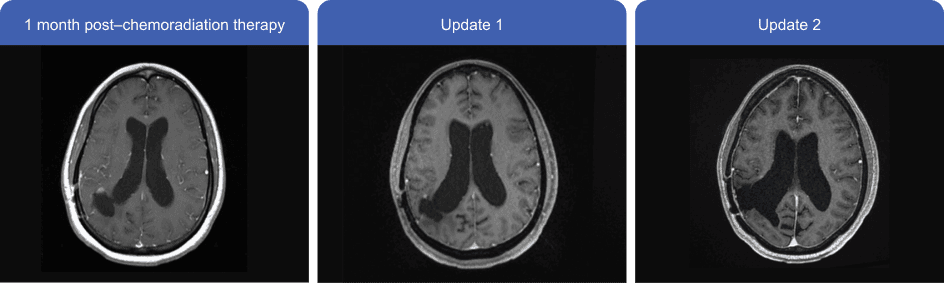

Patient's MRI

Case information used with permission from Volker Stieber, MD.